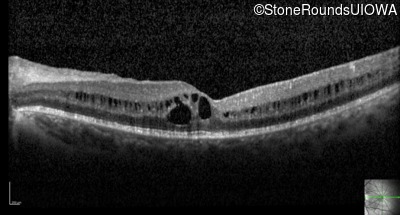

Optical Coherence Tomography - Left - 20/20 -2

Exemplar / OCT Stack

OCT Stack